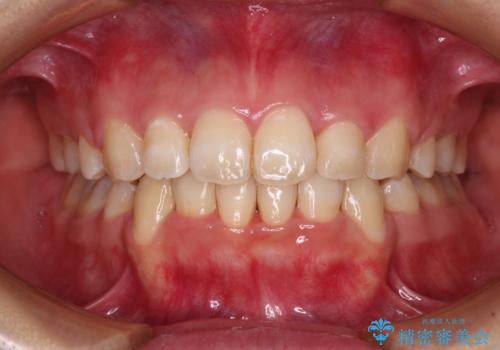

前歯の出っ歯と口の閉じにくさを抜歯矯正で改善 目立たないワイヤー矯正

掃除しにくい前歯と閉じにくい口元 目立たないワイヤー装置での抜歯矯正